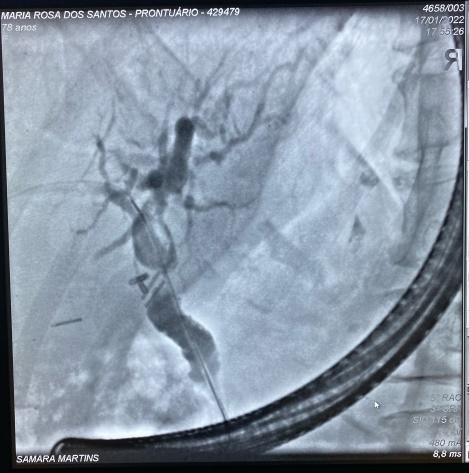

Paciente manteve assintomática e acompanhamento ambulatorial para programação de tratamento definitivo, que foi optado pela dilatação da via biliar (balão CRE 6-8mm) e inserção de prótese metálica auto-expansível totalmente recoberta (10 x 80mm) (Fig 5). O procedimento foi realizado 90 dias após a primeira CPRE sem intercorrências e optado pela retirada após 1 ano. A última CPRE foi realizada 12 meses após a inserção da prótese metálica no qual foi possível retirá-la, extrair o cálculo da via biliar proximal e obter uma colangiografia sem sinais obstrutivos ou extravazamentos ao final do procedimento (Fig 6).

Fig 5. Imagens colangiográficas da segunda CPRE: A. Imagem colangiográfica mostrando coledocolitíase proximal e subestenose em topografia de clipes; B. Imagem colangiográfica dilatação com balão em via biliar; C. Imagem radiológica da prótese metálica auto-expansível.